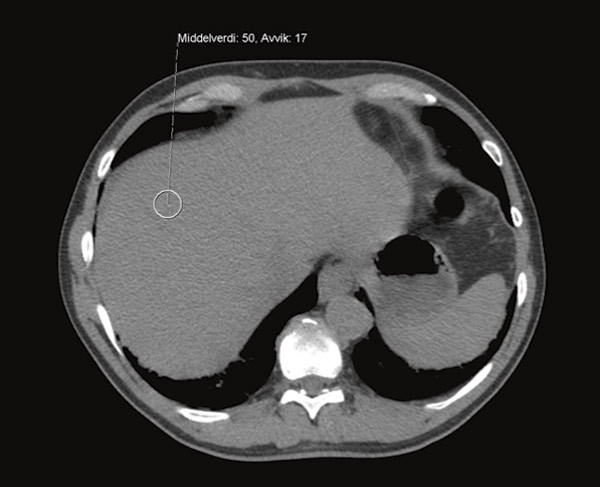

A CT examination of the liver was carried out that showed a pathologically elevated signal with average density 100 HU (Hounsfield units) (Fig. 2, Fig. 3), clearly consistent with iron accumulation in the liver. In the light of these findings, the probability of toxic overload in the liver was regarded as so great that the risk associated with a liver biopsy was not justified. An MRI cor was also carried out at the university hospital, where a T2-weighted image showed maximum pathological values of < 10 ms (> 20 ms), consistent with iron accumulation in the myocardium (Fig. 4). We found no validated method of measuring iron accumulation in the pancreas and thyroid.

Figure 2   CT abdomen without contrast from patient without pathological changes